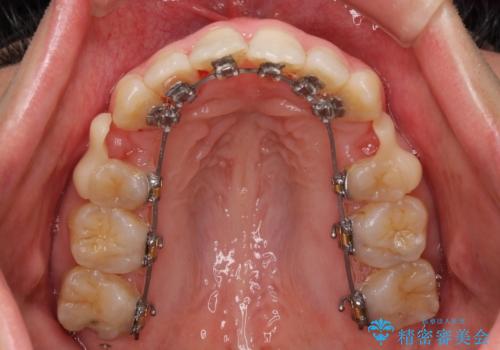

- 矯正装置

- ハーフリンガル

- 口元の突出感を気にして来院された患者様です。

上下左右の第一小臼歯4本を抜歯して口元を下げる治療計画としました。

舌の突出癖が強く、口元を引っ込める力に拮抗してしまい、抜歯スペースを閉じるまでに時間がかかりました。

また途中出産もありましたが、無事に治療を終えることができました。